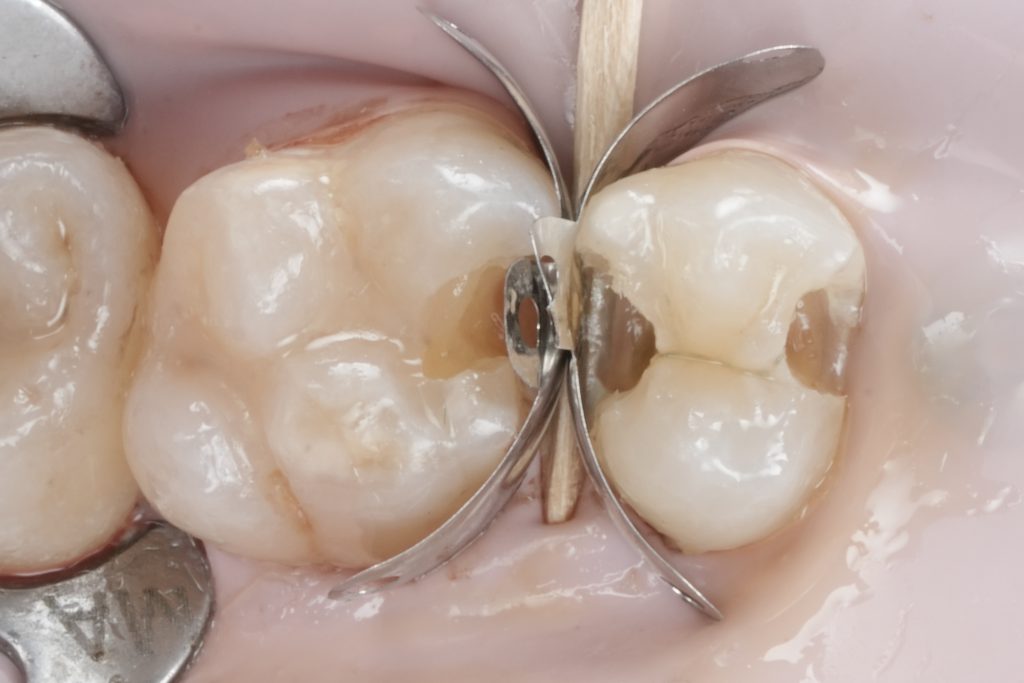

Images to place

- Fig. 7: Sectional matrix + wedge placed.

- Fig. 8: Ring in place (occlusal view showing band adaptation).